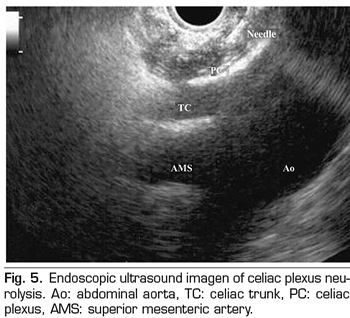

Endoscopic ultrasound offers the advantage of larger visualization of the celiac plexus at a short proximity, allowing larger precision and safety in the administration of the neurolytic agent and avoiding injection into vascular structures through the use of Doppler (37) (Figure 5). However, the studies supporting endoscopic ultrasound neurolysis, considered similarly to percutaneous technique as a rescue therapy, are limited to retrospective uncontrolled studies (38). Pauli et al. published a meta-analysis that concludes that this technique achieves an 80% pain reduction in patients with pancreatic cancer (39). Some studies show a slight decrease in opioid consumption, but without strong scientific evidence.

Regarding adverse effects, they are reported in a limited series of retrospective publications and case series, being hypotension (11%), diarrhea (18%), and transient abdominal pain (1.5 to 8%) described (37). Theoretically, this technique is safer, with its anterior approach through the gastric wall and direct passage of the needle to the plexus visualizing the vessels, without having to cross the retrocrural space (41). Even so, fatal complications have also been published with this technique. Gimeno-García et al. (42) described the first complication of thrombosis and vasospasm of the celiac artery that produced a multiorganic ischemia and the death of the patient. Since then, this complication has been published in 2 other studies, which also ended in death (43,44). Other adverse effects described are retroperitoneal bleeding and 2 cases of paraplegia.